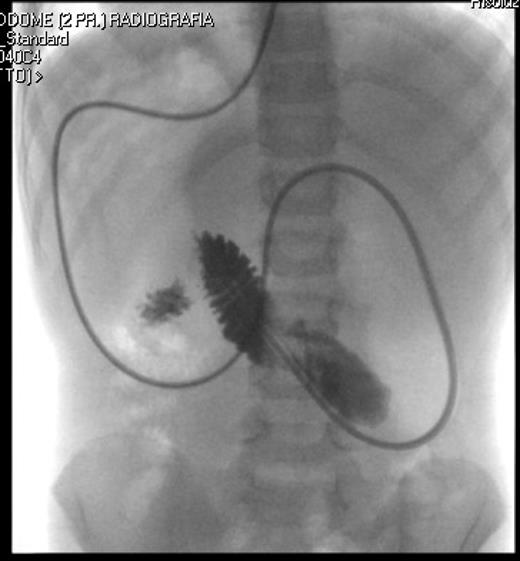

A 7-year-old boy who had been treated at 3 years of age for a subtotal colonic Hirschsprung disease with a Deloyers’ procedure was admitted for persistent bilious vomit associated with recurrent episodes of postprandial abdominal pain and diarrhea. The parents reported a progressive weight loss of 3.5 kg during the last 3 years. The patient was emaciated with severe chronic malnutrition; the weight and the length were 15.19 kg and 113 cm [body mass index (BMI): 11.9 kg/m2], both between the third and the fifth percentile, respectively. The clinical abdominal examination was normal. A plain abdominal X-ray showed a distended stomach with paucity of gas in the distal bowel. An abdominal ultrasound confirmed a dilated duodenum without signs of mechanical obstruction of the small bowel and a normal relationship between the superior mesenteric vessels. An upper gastrointestinal contrast study confirmed dilatation of the first and second portions of the duodenum with little progression of contrast medium across the third portion released in left lateral position (Fig. 1). An SMAS was confirmed by a computed tomography (CT) scan that showed a reduction in retroperitoneal preduodenal and mesenteric fat and compression of the third duodenum by the superior mesenteric artery with an acute 13° angle and a 7.5 mm distance from the aorta (Fig. 2). A gastrointestinal endoscopy confirmed the dilatation of the duodenum with an inflammatory mucosa and a normal jejunum. Gastric and duodenal biopsies were performed and a nasojejunal tube was guided through the duodenum to the Treitz to start enteral feeding (Fig. 3).

Correct position of the nasojejunal tube after endoscopic placement.